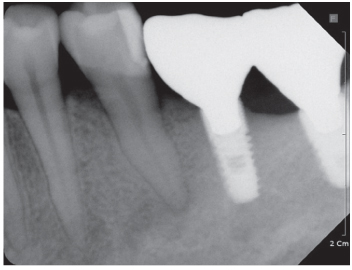

Figure 4

Location of mental foramens (dotted line) and periapical radiolucency (arrow).

Figure 4 Location of mental foramens (dotted line) and periapical radiolucency (arrow).